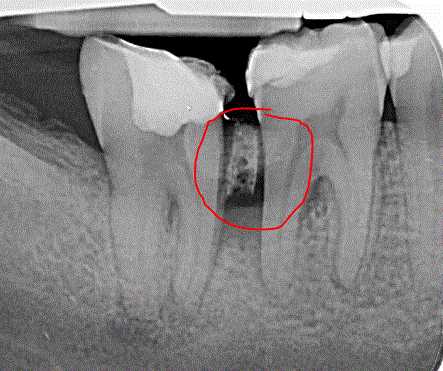

Q

Welche Art der Aufnahme

Was auffällig